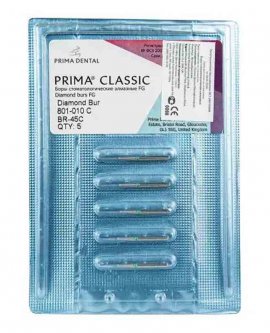

Ürünlerimiz